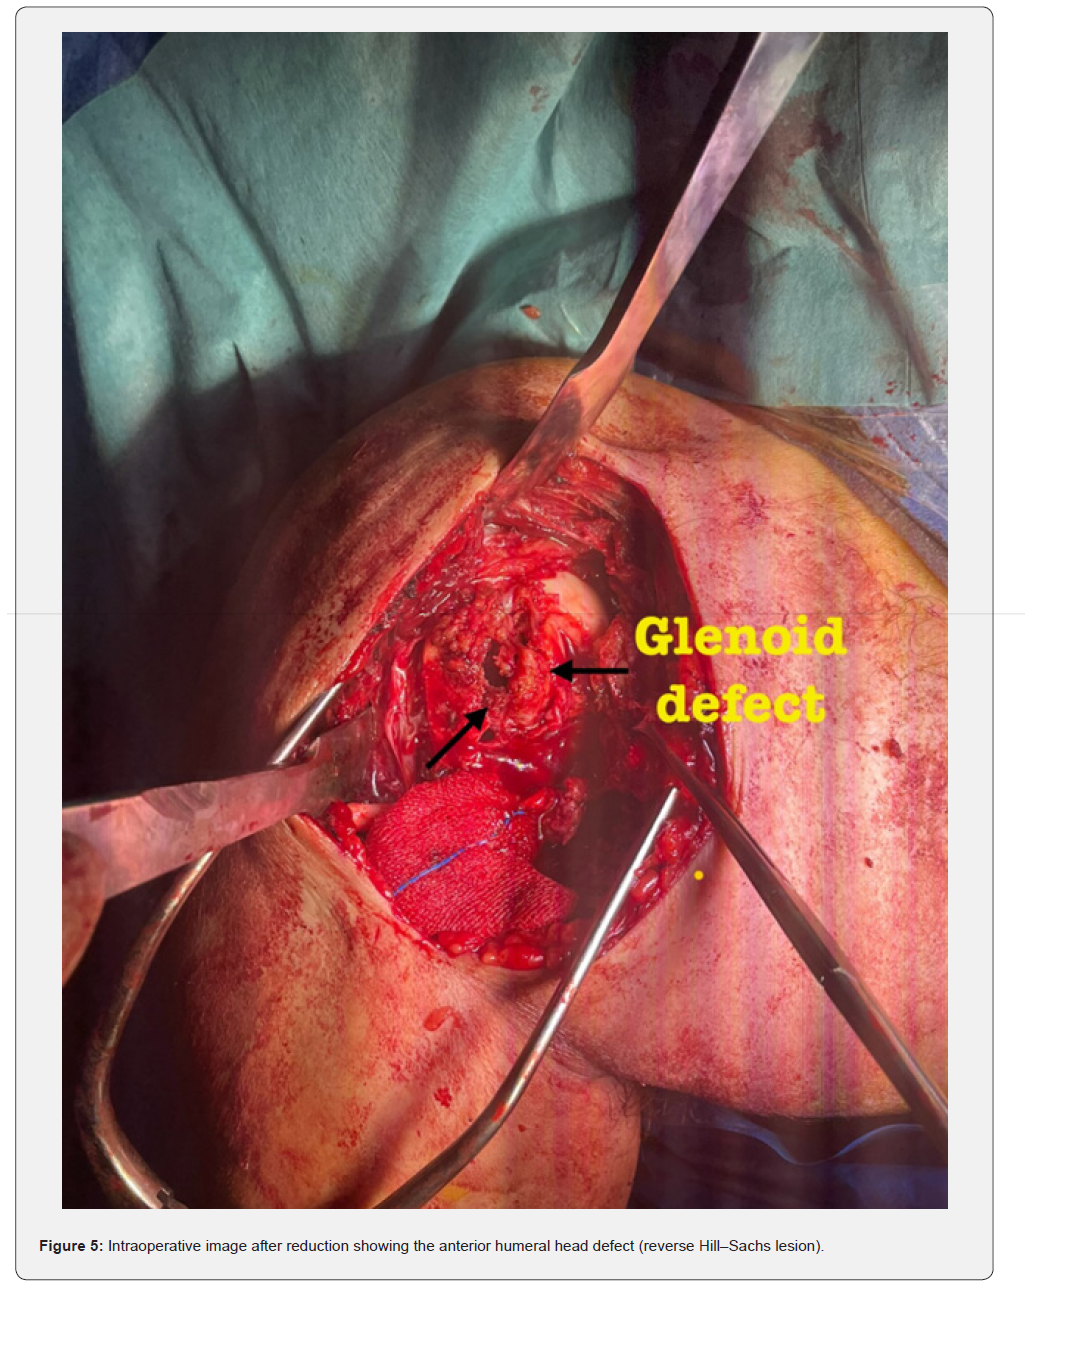

The patient was placed in a beach-chair position under general anesthesia. A standard deltopectoral approach was used. Intraoperatively, the humeral head was found locked posteriorly with fibrous tissue interposition (Figure 4). Open reduction was achieved after careful release of fibrous adhesions and identification of the anterior glenoid defect (Figure 5). The reverse Hill–Sachs defect was managed by a modified McLaughlin procedure: transfer of the subscapularis tendon into the defect using a suture anchor (Figure 6). Fixation was reinforced with two 3.5 mm cancellous screws with washers for stability (Figure 7). Intraoperative fluoroscopy confirmed concentric reduction and stable fixation (Figure 8). External and internal rotation was tested intraoperatively and demonstrated a stable, congruent reduction without evidence of redislocation or subluxation (Figure 9a–9b).